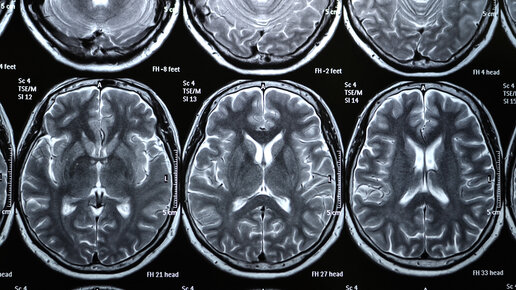

МРТ (магнитно-резонансная томография) – метод компьютерной диагностики с применением высокоточного современного оборудования. Благодаря ему можно выявить опасные заболевания на ранней стадии, предотвратить тяжелые последствия...